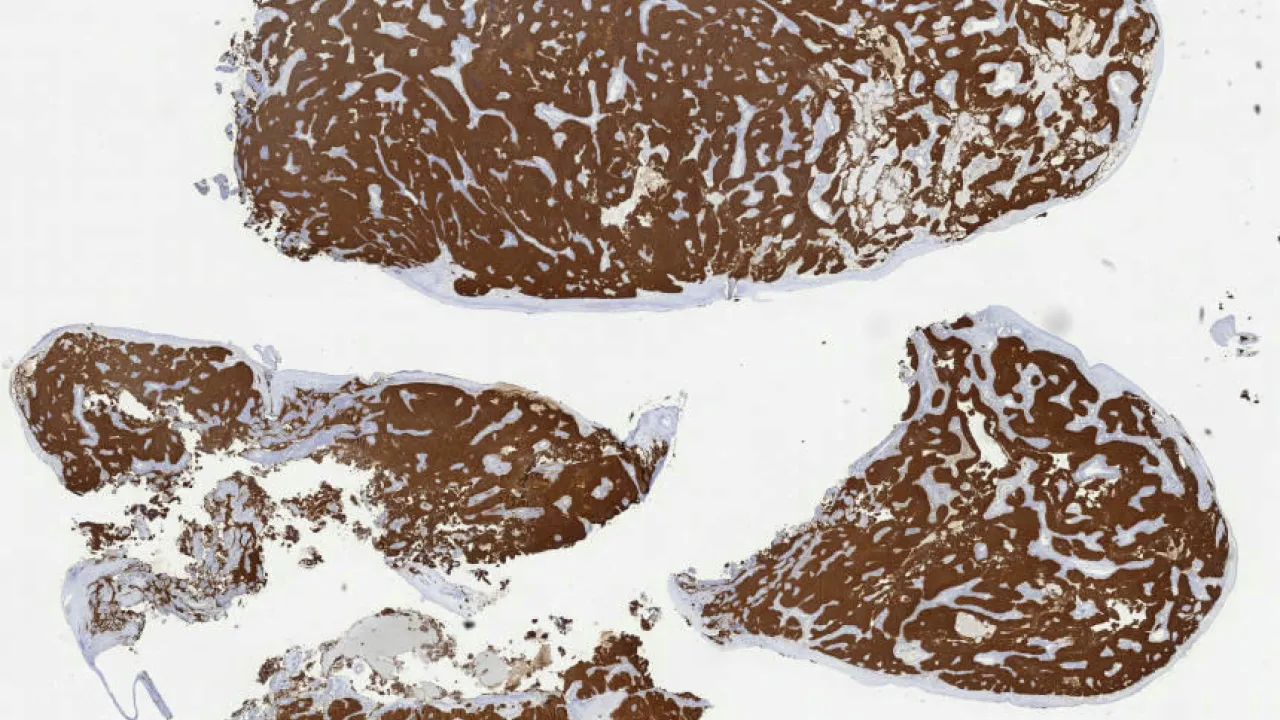

Skin, Involuting infantile hemangioma, GLUT1 stain